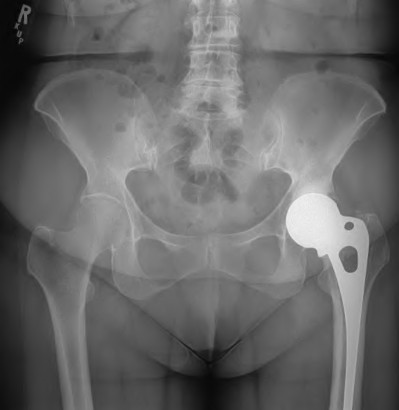

ORTHOPEDIC MCQS ONLINE RECON OB 20 1C 2020 A 72-year-old female presents with progressive left thigh and knee…

Orthopedic MCQS Reconstruction Adult Reconstructive Surgery of the Hip and Knee Scored and Recorded Self-Asse…